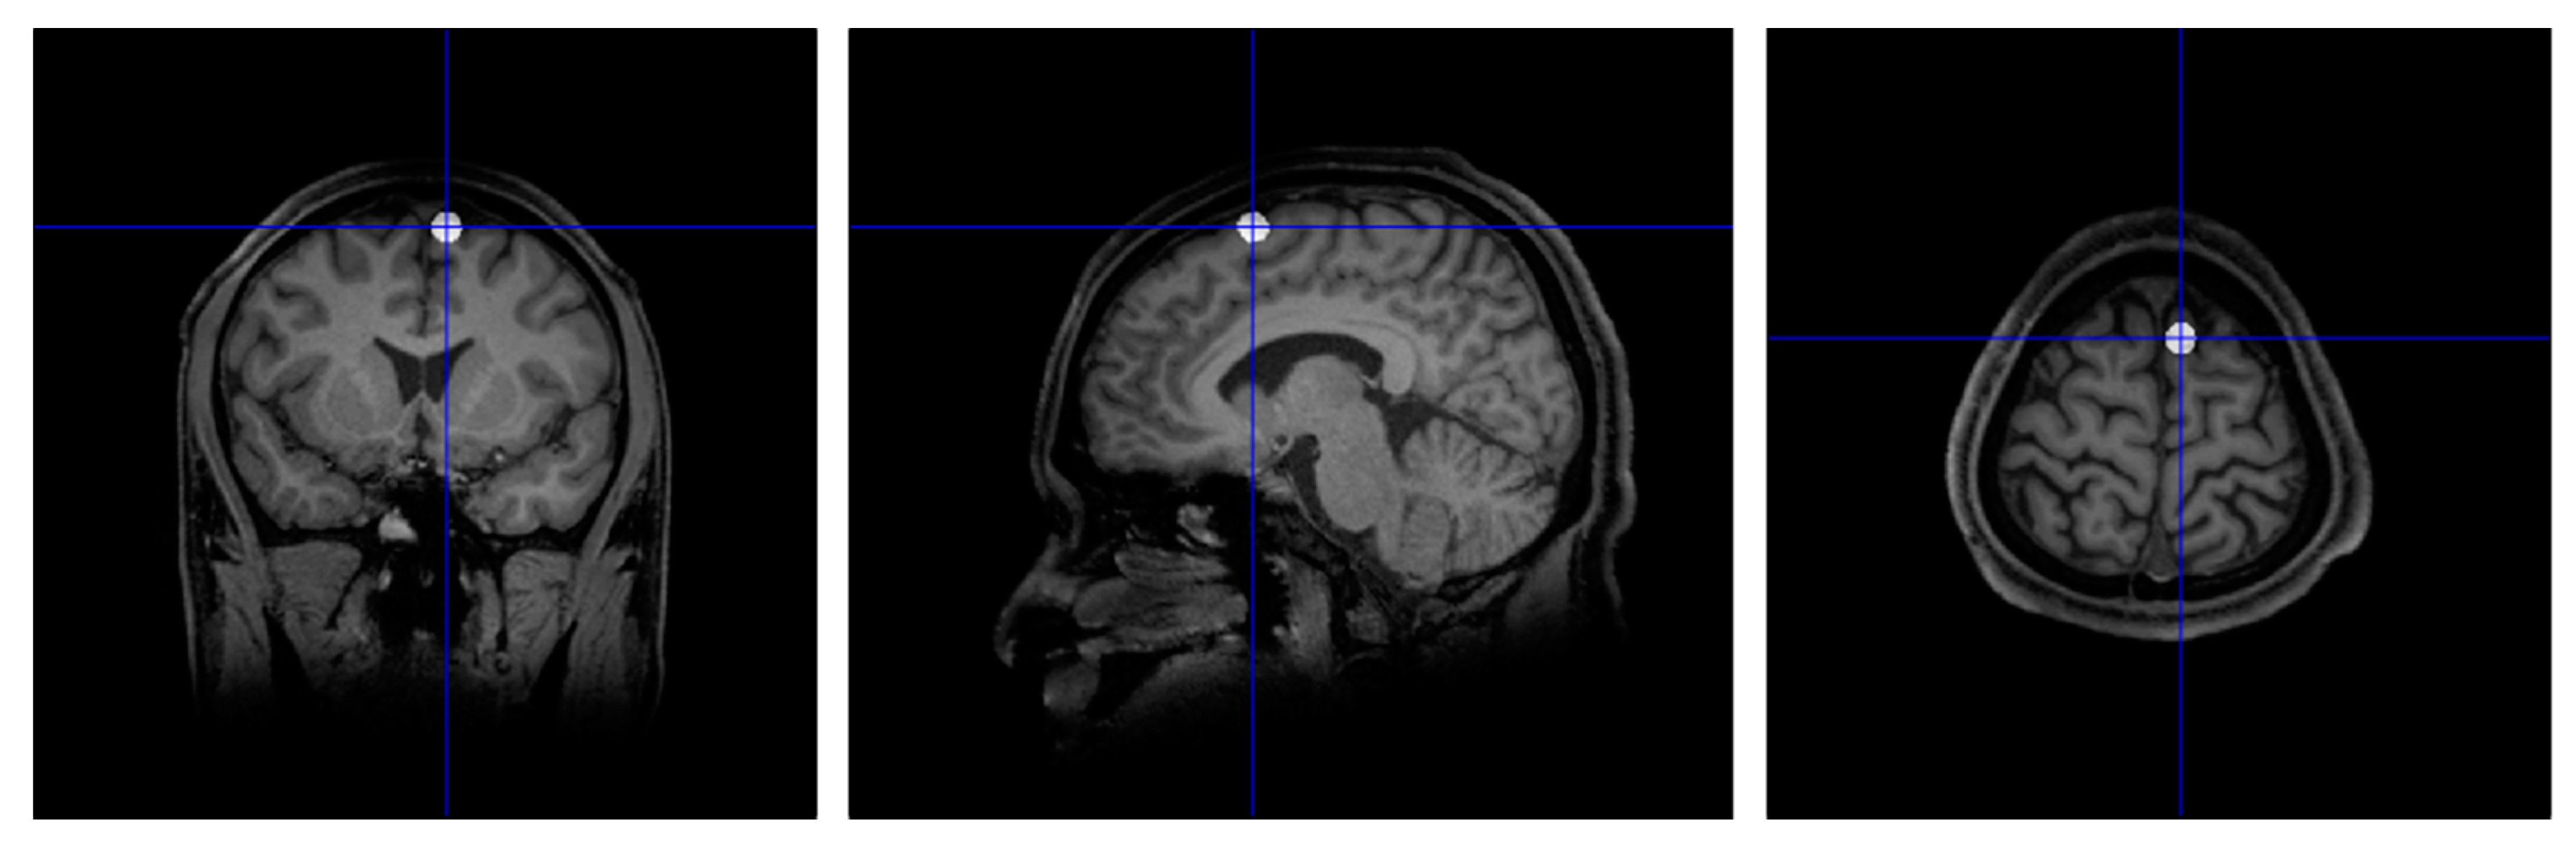

3.1.2. Target Localisation

3.1.3. TMS Procedure